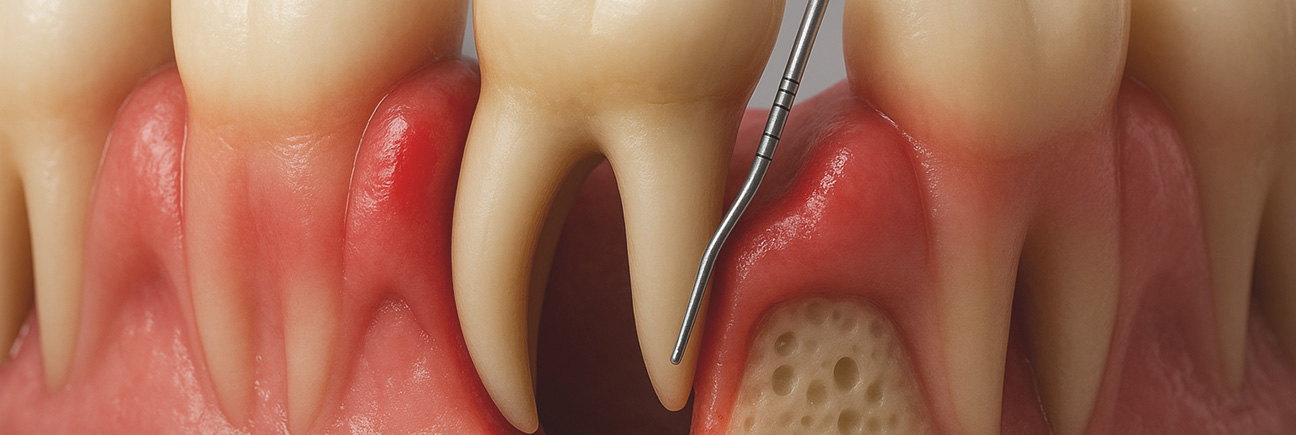

健康な歯と歯周病の歯の断面図

歯周病は、歯周組織(歯を支える歯茎や骨)が歯周病菌によって炎症を起こしている状態のことを指します。

初期の段階では、ほとんど自覚症状がなく、気づかないうちに進行してしまうことが多いです。しかし、症状が現れ始めると、歯茎(歯肉)が腫れて赤くなったり、触ると痛みを感じることがあります。

このような状態が続くと、歯茎から出血が見られることもあります。特に歯磨き時や食事の際に出血が起こる場合、歯周病が進行している可能性があります。

3. 03歯周ポケットの画像

歯周ポケットの測定

歯周ポケット(歯と歯茎の間の隙間)の深さを専用の器具(歯周プローブ)で測定します。正常な深さは1~3mmですが、4mm以上の深さがある場合、歯周病の進行が疑われます。